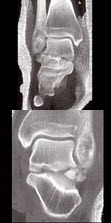

272、单项选择题

男,28岁,从高处坠落后双足疼痛1月余,结合影像学检查,最可能的诊断是()

A.跟骨骨折

B.骰骨骨折

C.距骨骨折

D.舟状骨骨折

E.楔骨骨折